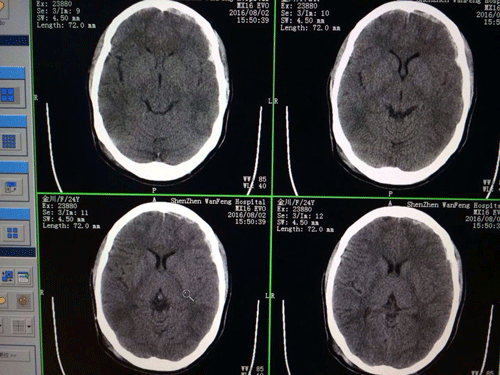

深圳万丰医院及时为伤者开通绿色通道,只要与抢救有关,各部门、各科室绝不讲价,无条件地全力以赴。急诊科首先通知外科洪和贵主任和产科刘学勤主任前来会诊。刘学勤主任在胎心监测的同时,对胎儿进行了一系列检查,未发现异常。洪主任通过CT影像判读和其他辅助检查综合分析,初步诊断金女士为脑挫裂伤、蛛网膜下腔出血、硬脑膜下血肿、颅右枕骨多发骨折。由于颅内压较高,患者出现严重呕吐,且意识不清、答非所问,甚至不能辨认身旁的丈夫。一个孕妇遭此横祸,而且损伤都集中在颅脑,预示着病情重笃。

时间就是生命,而且这场抢救关系到两条人命,不仅要抢救大人,还要顾及腹中的胎儿。此时,只能在保证胎儿安全的情况下进行保守治疗,洪主任为了确保治疗方案的准确性,及时将CT影像发送至市二院神经外科进行会诊,会诊意见原则上同意深圳万丰医院的诊断结果和治疗方案。以降低颅内压,消除应激反应,抗炎并消除脑水肿为关键,外科医生通过精心筛选后给药,使对胎儿的负面影响降至最低程度。

颅部CT影像

经过初期处理,金女士被转至外科重症病房进行特级护理。经过两天的精心治疗,4日上午经CT复查,伤者颅内出血已经停止,生命体征稳定,神志逐渐恢复,各项诊疗措施达到了预期的效果。